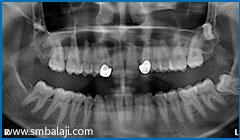

3D Cone Beam CT (CBCT) image showing impacted tooth and cyst in lower jaw right side

X-ray showing right lower impacted tooth with cyst lesion and other multiple impacted teeth